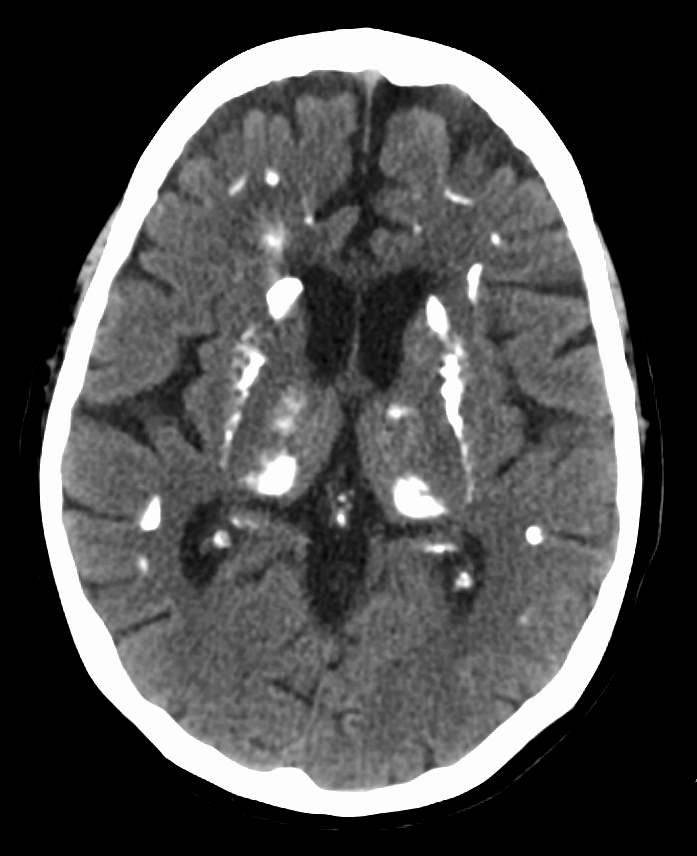

고칼슘혈증으로 인해 다양한 증상이 나타날 수 있는데, 흔한 증상으로는 변비, 구토, 권태감, 무기력증, 피로, 우울증, 뼈 통증(골통), 근육통, 관절통, 식욕 감퇴, 오심, 복통, 췌장염, 소변을 자주 보는 다뇨증, 심한 갈증, 인지 장애, 신결석, 현기증 등이 있다.[9][10] 또한 골밀도가 낮아지는 골감소증이나 골다공증이 발생할 수 있으며,[9][10] 방광결석이 생기기도 한다. 뼈 흡수가 진행되면 라켓 손톱(단지증)이 나타날 수 있고,[11] 방사선 사진에서는 럭비선수 척추라는 특징적인 소견이 관찰되기도 한다.[12] 신결석은 특히 흔한 초기 증상 중 하나인데, 이는 고칼슘혈증으로 인해 소변으로 배출되는 칼슘 양이 증가하고(고칼슘뇨증), 동시에 높은 PTH 수치로 인해 소변의 인산염 배설도 늘어나면서 칼슘과 인산염이 결합하여 결석을 형성하기 쉽기 때문이다.[7][8] 임상 검사에서 부갑상선 선종이 발견되는 경우는 매우 드물다.

고칼슘혈증 상태에서는 다른 혈액 검사 소견도 나타날 수 있다. 예를 들어, 고염소혈증이 동반되거나 신장에서 중탄산염의 손실이 증가하여 정상 음이온 차이를 보이는 대사성 산증이 발생할 수 있다.[60] 또한, 뼈의 교체율(turnover)이 증가하면서 알칼리성 인산가수분해효소(ALP) 수치가 상승할 수 있다. 원발성 고칼슘혈증의 경우, 혈청 칼슘 수치가 높음에도 불구하고 ALP 수치가 정상 범위 내에 있을 수 있지만, 이는 칼슘 수치를 고려했을 때 부적절하게 정상인 것으로 해석될 수 있다.